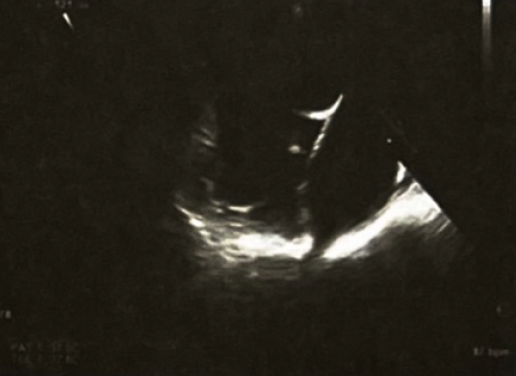

◆经食管超声心动图:左心耳未见血栓(图4)。

图4. 经食管超声心动图